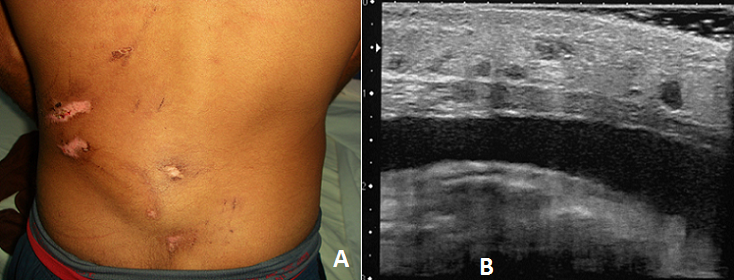

Le syndrome de Morel-Lavallée correspond à un épanchement sérolymphatique secondaire à un traumatisme tangentiel en regard d'un tissu richement vascularisé. Les aspects morphologiques sont variables en fonction de la durée d'évolution et de l'organisation éventuelle d'une capsule fibreuse. Le traitement conservateur associe bandage compressif et ponctions-aspirations. Le traitement chirurgical doit être envisagé dans les formes résistantes. Nous rapportons l'observation d'un homme âgé de 22 ans, sans antécédents pathologiques, qui avait présenté, à la suite d'un accident de la voie publique; motocycliste heurté par une voiture où il a été trainé par terre, plusieurs plaies au niveau de l'hémi-abdomen gauche qui avaient été suturées. Le scanner abdominal a montré un foyer de lacération splénique avec intégrité du pédicule, et un hémopéritoine de faible abondance. Devant la stabilité hémodynamique on a opté pour un traitement non opératoire qui a été un succès. Trois semaines après, le patient présentait une douleur lombaire gauche. Il avait une plaie fibrineuse en regard d'un œdème douloureux lombaire gauche. La palpation trouvait une masse fluctuante sous la plaie. Il y avait un syndrome inflammatoire biologique. L'échographie des parties molles identifiait une collection liquidienne anéchogène homogène extra-aponévrotique lombaire gauche. Le diagnostic d'épanchement post-traumatique de Morel-Lavallée a été retenu. Il a été réalisé à deux reprises à dix jours d'intervalle, une ponction évacuatrice de la collection ramenant respectivement 120 cc et 70 cc de liquide séro-hématique, un pansement compressif puis une contention. Les suites étaient favorables avec amélioration de la symptomatolgie et dispariton de la collection lombaire.